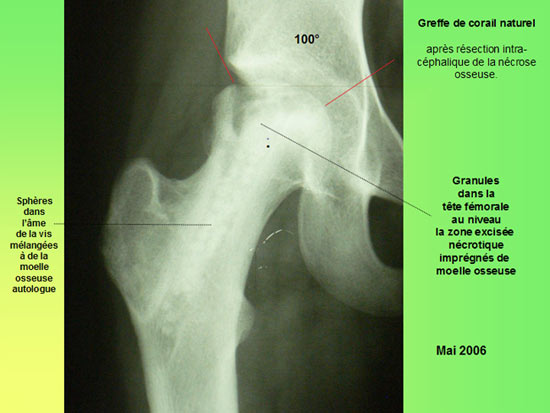

Technique opératoire Le trocart est introduit par voie pertrochantérienne et suit le trajet de la vis. Sa position dans la tête fémorale et dans la nécrose est repérée sous amplificateur de brillance de face et de profil. Une petite pince à séquestre retire les tissus fibreux et nécrosés circonférenciellement après repérage. Un lavage au sérum bétadiné complète le curetage. La moelle osseuse est prélevée (à l'aide du trocart de Mallarmé) sur la crète iliaque selon la technique classique. La moelle recueillie est d'autant plus riche en cellules souches qu'elle a été aspirée par petites fractions (2 ml). Ceci permet de réduire le degré de dilution par le sang périphérique. Elle est ensuite mélangée extemporanément avec le biomatériau. En général : 5 ml pour 5 cc de corail naturel. Sous contrôle Rx., le greffon est introduit à l'aide d'un trocart jusque dans la tête au niveau de la zone curetée : L'appui-contact avec 2 C.B est immédiat. Faut-il mettre en décharge avec traction et combien de temps ? Il ne sera possible de répondre à cette question que lorsque l'on saura avec précision la durée des phases de déminéralisation-reminéralisation du composite biomatériau-moelle osseuse aboutissant à de l'os néo- formé mécaniquement solide. C'est aux fondamentalistes de nous apporter la réponse.

Que se passe t'il à l'intérieur de l'os ? Clichés comparatifs intermédiaires - A : L'IRMN avant la greffe de biomatériau montre l'étendue de la nécrose sur la hanche de face. - B : L'IRMN postopératoire à 10 mois précise l'étendue de la nécrose dans la tête fémorale « in situ ». - C : Les Rx standards pré et postopératoire à 16 mois précisent l'évolution de la nécrose. - D : Les Rx standards post - opératoire à J + 1 et à 16 mois précisent l'évolution du biomatériau. ETENDUE de la NÉCROSE

Sur le plan radiographique : - La zone nécrotique est nettoyée. - L'aplatissement de la tête fémorale ne s'est pas aggravé depuis l'intervention. - le corail naturel est résorbé au niveau du col ; il est partiellement résorbé au niveau de la tête fémorale.